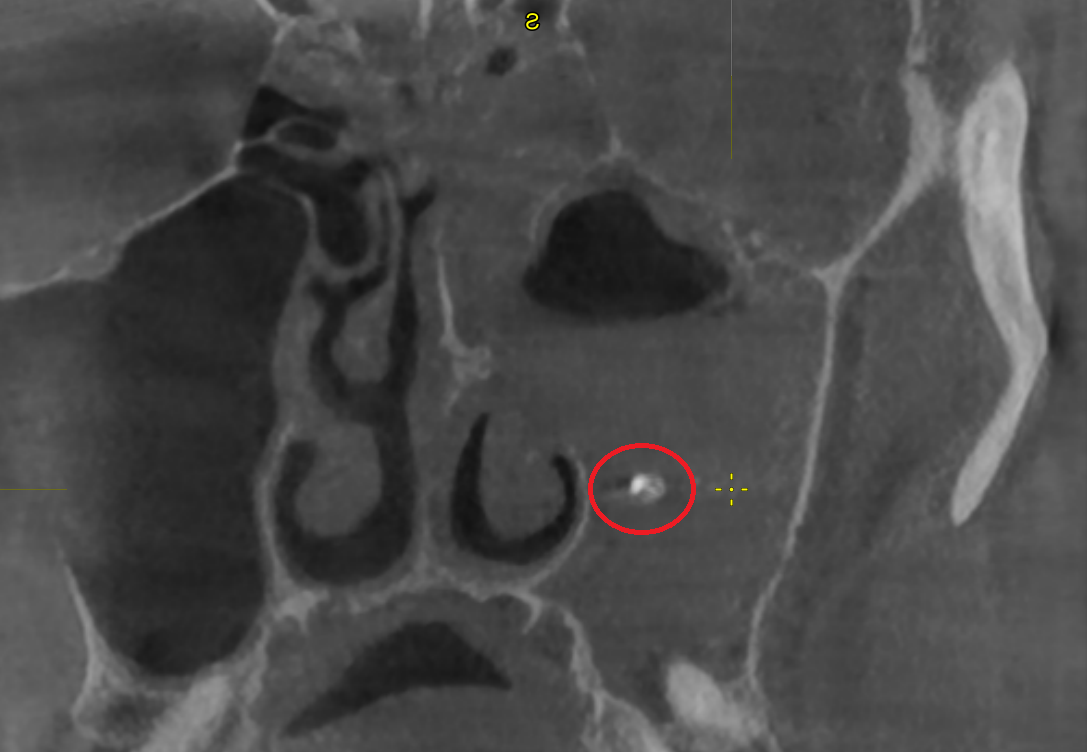

В красном кружочке - корень зуба, оказавшийся не на своём месте. Серое вокруг - воспаленная слизистая пазухи и гной.

Ключевым этапом стала визуализация: чаще всего выполняется компьютерная томография околоносовых пазух (КТ). На срезах у нашего пациента было видно выраженное утолщение слизистой оболочки гайморовой пазухи, жидкое соедржимое и самое главное — плотный фрагмент, идентичный по плотности зубной ткани, лежащий в просвете пазухи.

Так был поставлен диагноз: одонтогенный гайморит, вызванный попаданием корня зуба в левую гайморову пазуху во время сложного удаления. При подобных вмешательствах фрагмент корня может быть буквально «вытолкнут» в пазуху через образовавшееся отверстие между полостью рта и пазухой — ороантральное сообщение.